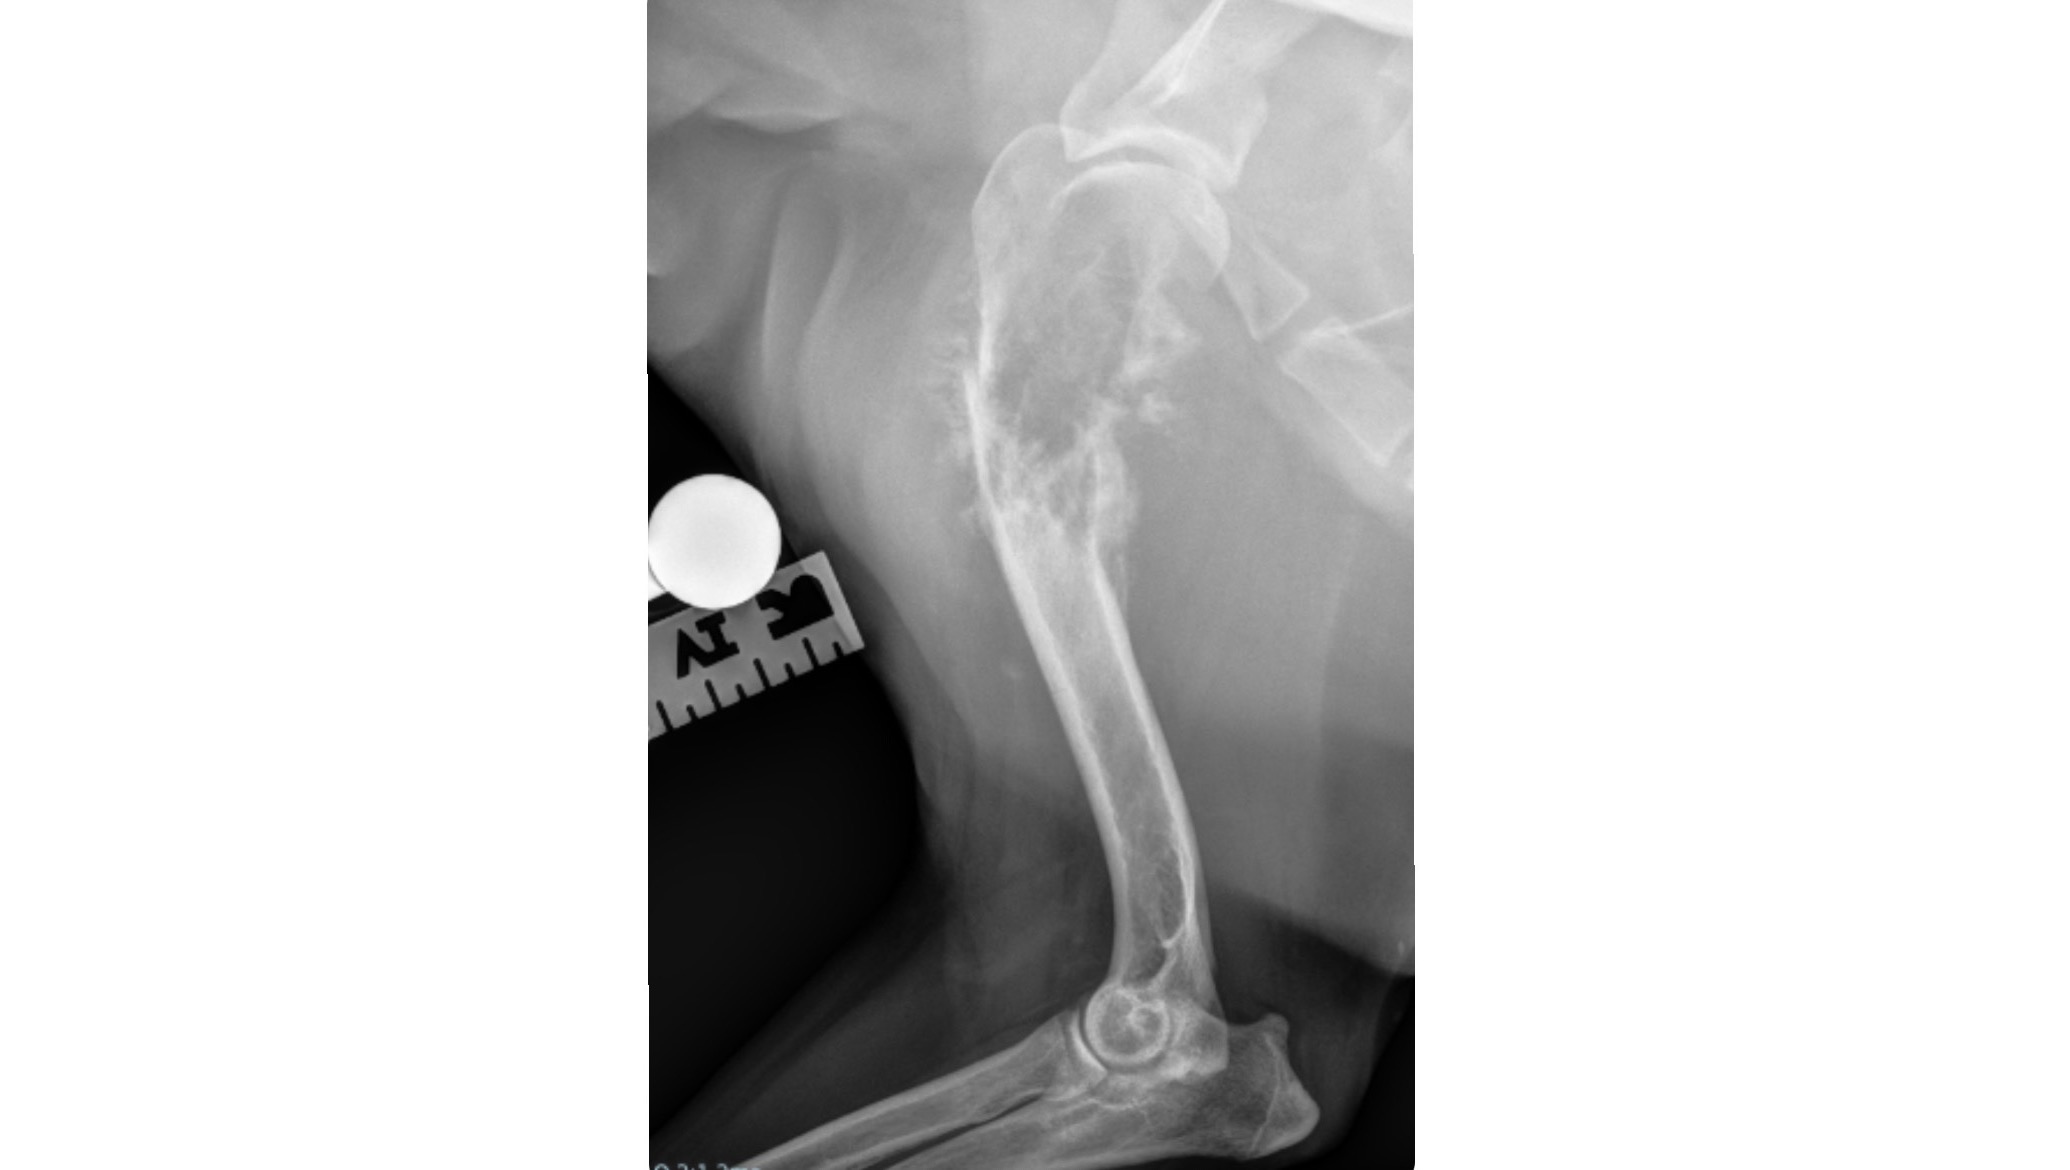

Last Thursday Beaux was not bearing any weight to his right front leg and was found to have a humerus fracture secondary to osteosarcoma, a type of aggressive bone cancer. For all of you who know Beaux, the sweetest boy whose got a lot of life and love to give. The doctor said it was either amputation or euthanasia as the humane thing to do given the painful nature of this type of cancer, and the bone being fractured. Beaux showed no sign of loss in energy or change in behavior so we agreed it wasn’t fair to cut his life short by putting him down.

Beaux got his right front leg amputated on Tuesday 3/12/24 and is finally home recovering, he’s showing extreme resilience and looks to be acclimating to life on three legs quite quickly. We know this will be an uphill battle but we are willing to do whatever it takes to ensure Beaux receives the best possible care and treatment to recover and thrive. We have created this GoFundMe to help cover the costs of his medical expenses including his amputation, medication, follow up appointments and chemotherapy. We appreciate any help during this tough time and thank you for your support.